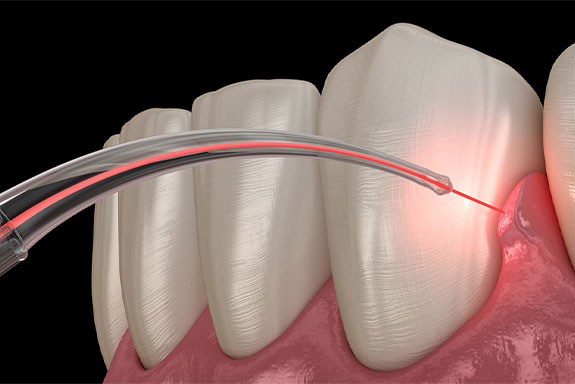

Laser dentistry is an innovative area of dental care treatment. In this process, lasers are used to provide relief to people suffering from a number of different dental ailments. Laser dentistry procedure offers a comfortable treatment option for different dental procedures which involve hard or soft tissue including treating gum disease, hypersensitivity, tooth decay, and whitening teeth. Lasers can make dental treatments more cost-effective and comfortable as compared to traditional drills and other dental instruments.

3. Gum Disease Treatment: Lasers are employed in treating gum disease by removing infected gum tissue and promoting gum reattachment. This procedure, known as laser-assisted periodontal therapy, helps reduce bleeding, swelling, and discomfort compared to traditional gum surgery.

4. Gum Reshaping: Dental lasers can reshape gum tissue to improve the appearance of a "gummy"smile or correct an uneven gum line. This procedure, called gingival contouring, provides precise results with minimal bleeding and faster healing.

8. Dental Surgery: Lasers are used in various oral surgeries, such as gum surgery, wisdom tooth extraction, and frenectomy (removal of oral tissue attachments). Lasers minimize bleeding,reduce the need for sutures, and promote faster healing.